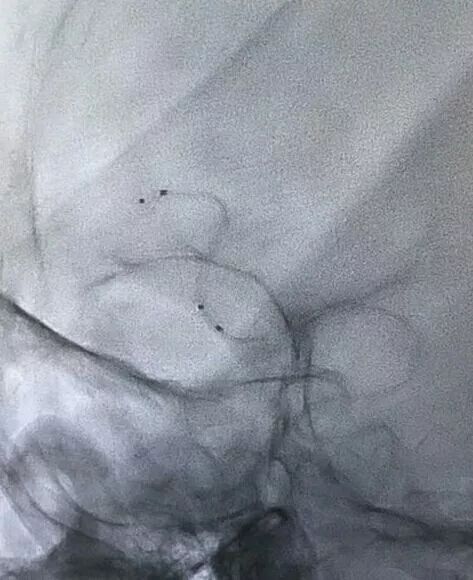

术后左侧颈内动脉造影,瘘完全不显影。

右侧颈内动脉造影,瘘亦不显影,大脑前动脉正常分支清楚展示。